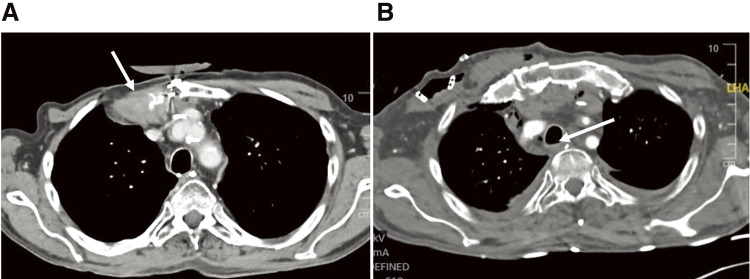

Case presentation: We report a case of a long tracheal membranous wall defect (> 7cm) after esophageal resection. We successfully performed a transtracheal direct repair of the defect through a partial sternotomy, and reconstructed the ventrolateral wall with a muscle flap using the right pectoralis major muscle.